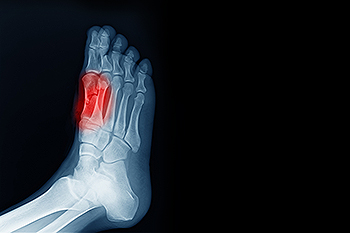

Tips for a Smoother Stride While Running With ArthritisArthritis can make running difficult, but the right adjustments help reduce pain and keep you active. Wearing the right footwear is essential. Well-cushioned, supportive running shoes or custom orthotics absorb...

Signs of Diabetic Peripheral NeuropathyDiabetic peripheral neuropathy is a condition caused by prolonged high blood sugar levels that damage the nerves, especially those in the feet, toes, and ankles. Many people first notice numbness, tingling, or burning sensations,...